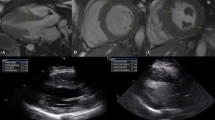

The agreement between TAPSEout and TAPSEin was analysed (Table 2). The limits of interobserver as well as intraobserver agreement for TAPSEout measurements were narrower than those for the TAPSEin measurements (Table 2, Fig. 2). Additionally, the coefficients of repeatability were lower for the TAPSEout measurements, indicating better reproducibility (Table 2).

Bland-Altman plots depict interobserver and intraobserver agreement regarding TAPSEout (a, c) and TAPSEin (b, d). On each plot, the solid line represents mean value of the differences between measurements between two observers (a, b) or between two observations (c, d). Dotted lines represent ± 2 SD. The mean value of the two measurements is plotted along the x-axis and the difference between two observer or observations is plotted along the y axis Abbreviations: SD standard deviation, TAPSE tricuspid annular systolic excursion